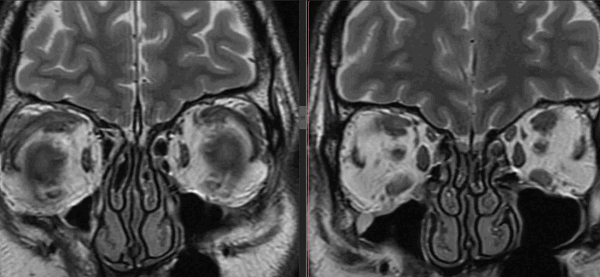

а, b Двусторонние внутриглазничные лимфомы. На Т1 -взвешенном изображении очаги выглядят как гипоинтенсивные объемные образования (а) с выраженным усилением после введения гадолиния (b).

КТ, МРТ при лимфопролиферативном образовании глазницы

Неходжкинская лимфома (случай сочетанного поражения глаз и орбиты)

В статье представлен полный клинический, инструментальный и морфологический анализ крайне редкого патологического состояния — сочетанного поражения глаз и орбиты лимфопролиферативным процессом.

Мужчина 52 лет обратился в нашу клинику с жалобами на выстояние левого глаза и двоение в течение 2 мес. Проведен анализ клинической симптоматики. Инструментальные методы исследования включали флюоресцентную ангиографию (ФАГ) (Digital retinal Camera CX-1, «Canon», Япония), высокоразрешающее ультразвуковое дуплексное сканирование (УЗДС) (Voluson 730 Pro, «General Electric Healthcare», Австрия), компьютерную томографию (КТ). Диагноз верифицирован с помощью цитологического и гистологического (отделение патогистологии института, руководитель — проф. И.П. Хорошилова-Маслова) методов исследования.

КТ позволила выявить ретробульбарную ткань с достаточно четкими границами, локализующуюся вокруг зрительного нерва, а также утолщение хориоидеи слева (рис. 4). Патологических изменений справа по данным КТ выявлено не было. С помощью УЗДС слева в В-режиме непосредственно за задним полюсом глаза (вокруг зрительного нерва) определяли гипоэхогенную, практически однородную опухолевую ткань с четкими неровными контурами. Одновременно выявили диффузное утолщение хориоидального слоя в области заднего полюса глаза — до 2,5 мм (рис. 5, а). Ультразвуковой денситометрический анализ, проведенный на основе двумерных серошкальных гистограмм, продемонстрировал крайне низкие значения акустической плотности ткани (А=3—12 усл. ед.) (см. рис. 5, б). В режиме цветового допплеровского картирования (ЦДК) отмечена гиперваскуляризация ретробульбарного и интраокулярных очагов с высокими линейными характеристиками кровотока. Следует отметить, что два указанных процесса — внутриглазной и орбитальный имели единую васкуляризацию (см. рис. 5, в). Патологических изменений в правом глазу по данным ультразвукового исследования выявлено не было.

Рис. 4. Компьютерная томограмма орбит в аксиальной (а) и сагиттальной (б) проекциях.

Рис. 5. Результаты дуплексного сканирования. а — утолщение хориоидеи; б — денситометрические показатели акустической плотности опухоли в В-режиме; в — множественные собственные сосуды опухоли, единая васкуляризация внутриглазного и орбитального очагов в режиме ЦДК.

Данные клинического и комплексного инструментального обследования позволили предположить лимфому с одномоментным вовлечением глаза и орбиты слева и начальный процесс с правой стороны.

Для подтверждения диагноза и определения дальнейшей тактики ведения больного первым этапом лечения была эксплораторная орбитотомия с биопсией образования. Во время операции непосредственно за глазным яблоком выявлена диффузно распространяющаяся опухолевая ткань светло-розового цвета с выраженной собственной сосудистой сетью, инфильтрирующая мягкие ткани орбиты, интимно контактирующая с задним полюсом глаза и оболочками зрительного нерва. Цитологически, иммуноцитохимически и гистологически была верифицирована В-клеточная лимфома (рис. 6), в связи с чем больной был направлен на консультацию к онкогематологам и нейрохирургам. Полное обследование у этих специалистов (включающее в том числе стернальную пункцию и магнитно-резонансную томографию головного мозга) не выявило патологии в других системах органов, в связи с чем процесс был расценен как первичная лимфома органа зрения с вовлечением обоих глаз и левой орбиты. Больному был назначен курс полихимиотерапии (ПХТ).

Рис. 6. Морфологическая картина. а — результат цитологического исследования. Обилие пролимфоцитов. Окраска по Паппенгейму. Ув. 1000; б — результат иммуноцитохимического исследования. Выраженная положительная реакция на CD20 (коричневое окрашивание); в — гистологический препарат. Окраска гематоксилином и эозином. Ув. 100 и 400. Разрастание лимфоидных клеток средних размеров (в 1,5 раза крупнее малых лимфоцитов) с ядрами округлой и неправильной формы, дифференцируются немногочисленные клетки более крупных размеров.

В настоящее время, спустя 6 мес после постановки диагноза и проведения 4 курсов ПХТ, состояние больного удовлетворительное. Патологических изменений со стороны ЦНС и других систем органов на данный момент не выявлено. Зрение обоих глаз с миопической коррекцией 1,0. Клинически отмечается положительная динамика в виде уплощения и уменьшения площади поражения (рис. 7, 8). Аналогичные результаты демонстрируют и инструментальные методы исследования (рис. 9). Однако в связи с наличием остаточного опухолевого процесса больной был направлен к гематологам для продолжения курса лечения (ПХТ).

Рис. 7. Офтальмоскопическая картина (а) и флюоресцентная ангиограмма (б) глазного дна левого глаза через 6 мес после ПХТ. Отмечается уплощение очага и уменьшение ретинального отека.

Рис. 8. Офтальмоскопическая картина (а) и флюоресцентная ангиограмма (б) глазного дна правого глаза через 6 мес после ПХТ.

Рис. 9. Дуплексное сканирование левого глаза и орбиты через 6 мес после ПХТ. Определяется уменьшение размеров опухолевой ткани в В-режиме (а), сохранность собственной васкуляризации в режиме ЦДК (б).